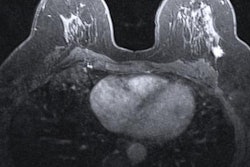

Artificial intelligence (AI) algorithms can improve the performance of breast MRI, both by helping women avoid benign biopsies and by predicting nodal metastasis so that clinicians can better plan treatment, according to research presented at the recent virtual American Roentgen Ray Society (ARRS) meeting.

In one study, researchers from the University of California, Los Angeles (UCLA) found that a machine-learning algorithm was able to help clinicians better categorize lesions with nonmass enhancement on breast MRI -- cutting the number of unnecessary biopsies by half.

Nonmass enhancement on breast MRI can be confounding, as it "presents with a varied appearance and considerable overlap between benign, high-risk, and malignant lesions," the group noted. "Although imaging features such as distribution, internal enhancement, and kinetics are used to characterize nonmass enhancement, biopsy is often required for definitive diagnosis with benign biopsy rates greater than 50% in certain large studies," it wrote.